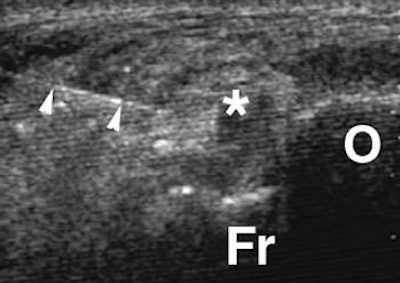

All the players had undergone physical rehabilitation but still developed posterior pain. Both noncontrast and contrast-enhanced MR imaging was done. Ultrasound exams were performed with a 10-15 MHz transducer (Antares, Siemens Medical Solutions, Malvern, PA; ATL 5000, Philips Medical Systems) to evaluate the posterior capsule tissues including a Doppler study of soft-tissue abnormality.

For the injection therapy, a 20- or 23-gauge needle was inserted directly to the abnormal area of the posterior capsule. Then, 40 mg of triamcinolone acetonide and 3 mL of 0.5% bupivacaine hydrochloride were injected into the abnormal tissues. If an os trigoum was present, the needle was moved on to the ossicle.

According to the results, all patients had posterolateral hypoechoic capsule thickening that was nodular and localized to the lateral aspect of the lateral talar process or os trigonum. All 10 patients tolerated the injection procedure with no immediate complications. They also reported ankle improvement after the bupivacaine shot.

![]() |

| Axial sonography image of os trigonum (O) and adjacent fragment (Fr) obtained during injection shows nodular synovitis (asterisk) with needle (arrowheads) placed during infiltration and injection. Further infiltration was performed around fragments. Robinson P and Bollen SR, "Posterior Ankle Impingement in Professional Soccer Players: Effectiveness of Sonographically Guided Therapy" (AJR 2006; 187:W53-W58). |

The median follow-up time was 26 months for all players. At this juncture, eight out of 10 patients with posterolateral synovitis and no os trigonum had no residual or recurrent symptoms. The remaining two players who did have posterolateral synovitis and os trigonum on imaging experienced a recurrence of symptoms and underwent repeat injection with ultrasound guidance. One player remained pain-free after the second session; the other required endoscopic resection.